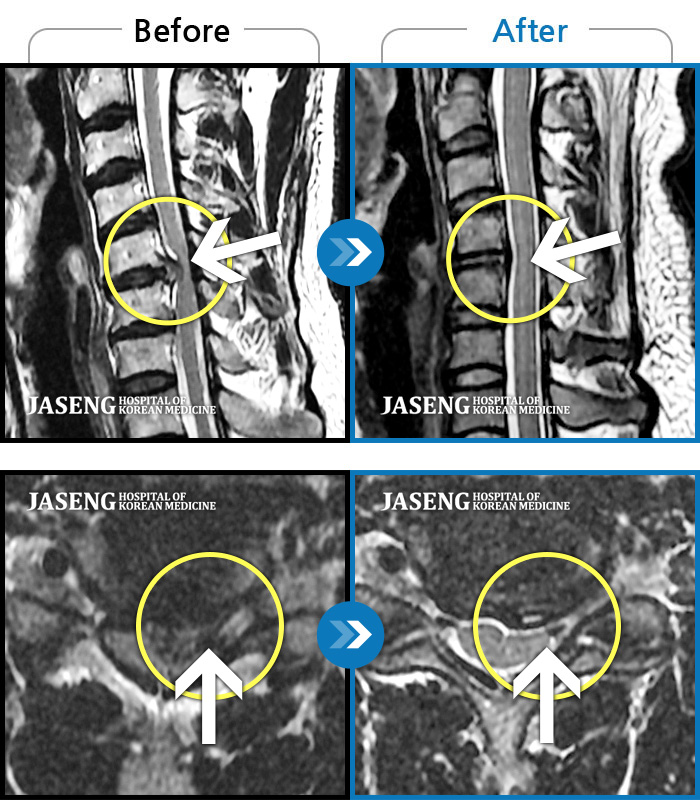

[뱸] 19.11.28~25.05.06

ȯںп Ǹ ǿ ԿǾ, ο ġ ۿ Ƿ ġḦ Ͻñ ٶϴ.